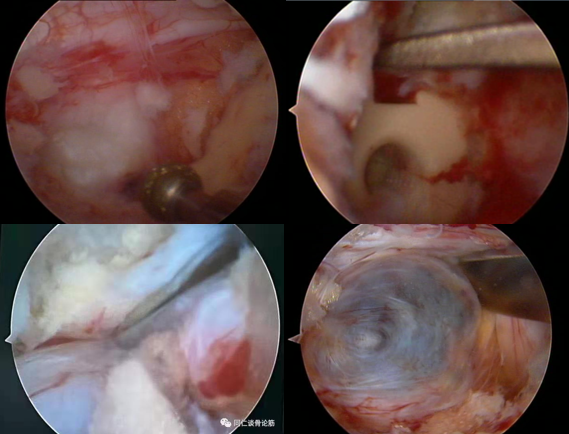

六、复发(2.27%)

病例(椎间盘突出复发)

女,42岁。

主诉:腰痛伴左下肢疼痛2月。

查体:疼痛放射至左侧臀部、大腿后侧、小腿后外侧。

思考和建议

完整切除突出的椎间盘

切除的椎间盘为影像学体积150%

视情况缝合纤维环,避免复发

七、术后椎间盘囊肿

病例

男,31岁。

主诉:腰痛伴右下肢疼痛5月,加重2月。

查体:疼痛放射至右侧臀部、大腿外侧、小腿外侧。